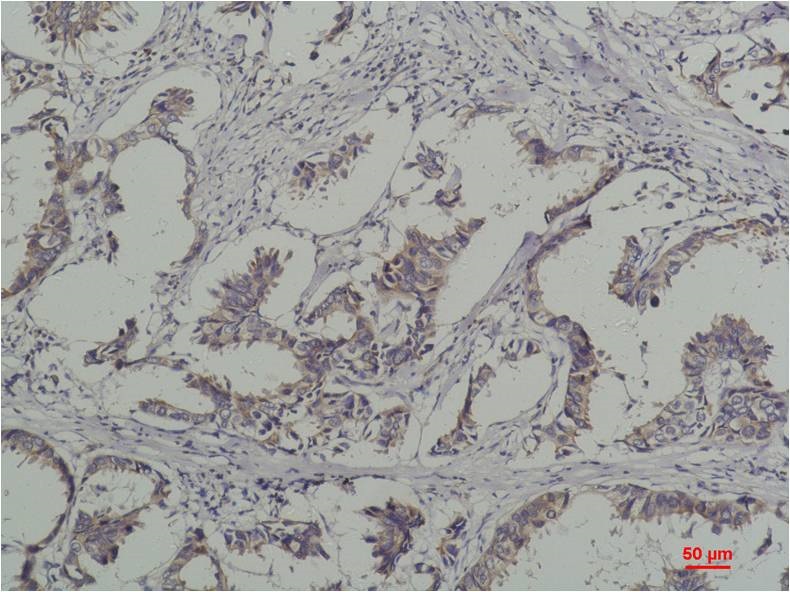

Immunohistochemical analysis of paraffin-embedded Human Breast Caricnoma using Phosphotyrosine(BE3431)Mouse mAb diluted at 1:200.